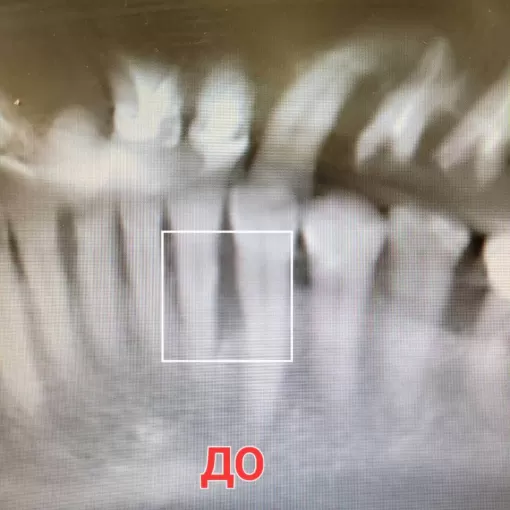

По данным КЛКТ в области зуба 4.6 был выявлен воспалительный очаг. Проведено эндодонтическое лечение с использованием микроскопа, с последующим протезированием коронкой из диоксида циркония.